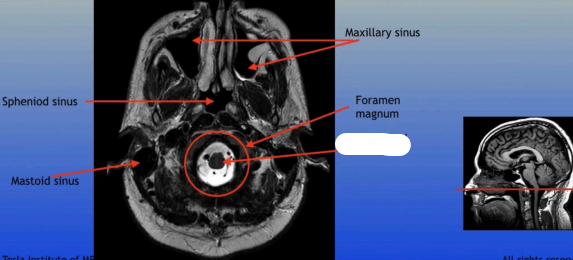

Maxillary Sinus

Sphenoid Sinus

Sphenoid Sinus

Mastoid Sinus

Maxillary Sinus

Foramen Magnum

Spinal Cord